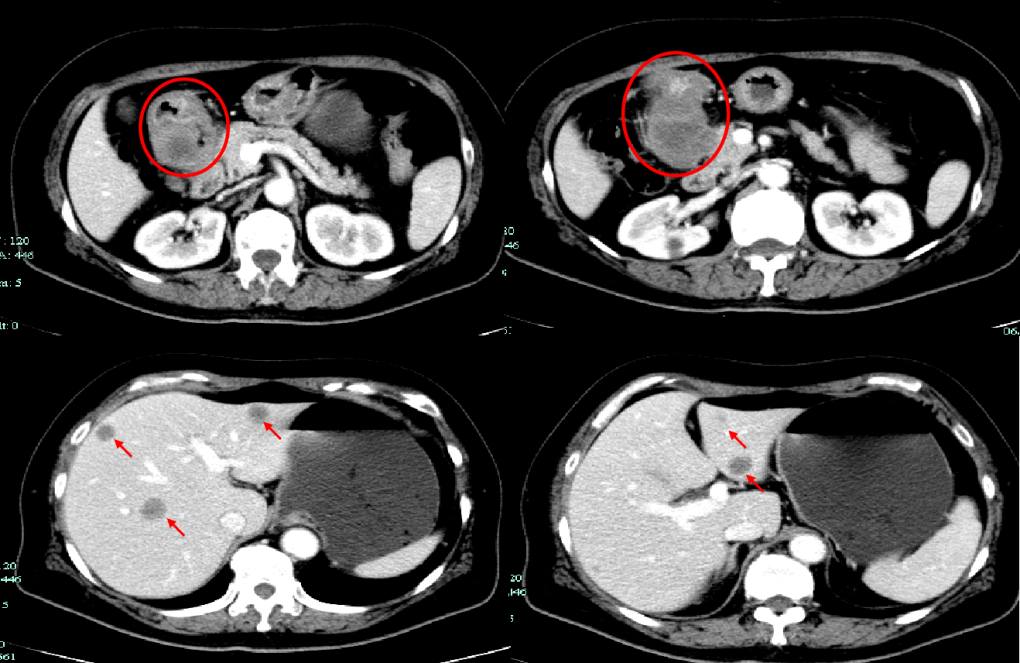

CT-T

CT-H1

MR-H1

影像学检查结果评估:cPD。